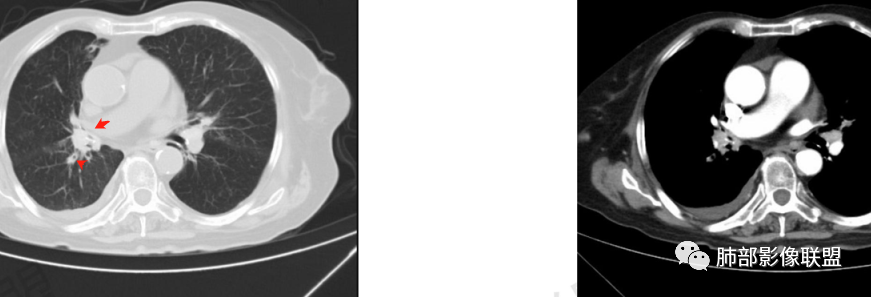

结核是肯定有。现在最大问题是尖段

近端显示不清,但是远端是粘液栓,可以认为是还行的

如果是近端鳞癌,远端应该会堵塞,不会整个肿块里面还有较为通畅的支气管

相应上叶尖端及前段支气管开口未能追踪(阻塞),开口处见钙化。病灶渐进性强化,并衬托出较完整尖段及前段含液支气管影。支气管开口区域未见异常高密度强化(如类癌等)及相对乏血供区(如鳞癌)。病灶区未见液化坏死。右上纵隔及胸廓入口区未见病灶胸膜外突破(栽赃)。